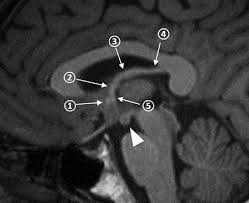

Where can we find mamillary bodies

posterior to optic chiasm

fornix

Limbic system, alternative visualization